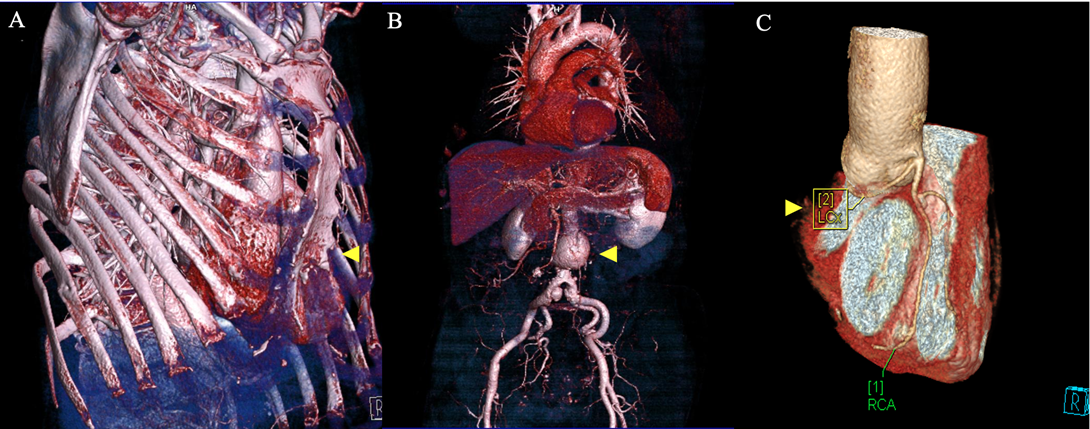

In total, 11 patients (13.9%) were excluded from MIMVS due to CT findings alone. CT exclusion criteria included: significant MAC (Figure 2A); significant coronary artery calcification (Figure 2B); dilatation of the ascending aorta to 4.4 cm (Figure 2C); significant mural thrombus in descending and abdominal aorta (Figure 2D); slender, calcified iliofemoral vessels (Figure 2E); dissection flap in the right external iliac artery (Figure 2F); incidental persistent left-sided superior vena cava (SVC) (Figure 2G); significant chest wall deformity (Figure 2H and 3A); incidental liver haemangioma (Figure 2I); 4.6 cm abdominal aortic aneurysm (AAA) (Figure 3B) and aberrant origin of the left circumflex artery (Figure 3C). A further 10 patients (12.7%) were excluded from MIMVS following multidisciplinary team (MDT) discussion due to: complexity of repair; non-isolated procedure and evidence of previous inferolateral myocardial infarction (MI). Additional CT findings resulting in modification of minimally invasive operative strategy included a partially bifid 4th rib (Figure 4A) and rib crowding (Figure 4B). Significant incidental findings that resulted in further investigation and referral to other pathways included a 10 mm lung nodule (Figure 5A) and 4 cm renal mass (Figure 5B).

Figure 3. Contraindications for minimally invasive mitral valve surgery (MIMVS). 3D CT reconstructions revealing: A) Significant pectus excavatum; B) 4.6 cm abdominal aortic aneurysm and C) Aberrant origin of the left circumflex artery: [1] RCA: Right coronary artery and [2] LCx: Left circumflex artery.

Significant coronary artery disease is a contraindication for MIMVS as patients will require concomitant coronary artery bypass grafting (CABG) via conventional sternotomy. Two patients were excluded from MIMVS due to significant coronary artery calcification (Figure 2B) that was initially picked up on CT and required referral for invasive coronary angiography. Both of these patients required concomitant CABG via sternotomy. The left circumflex artery (CxA) lies within close proximity to the posterior mitral valve annulus, this makes it susceptible to injury during MV surgery.12 Possible mechanisms of injury to the CxA include: direct laceration, occlusion with a suture, distortion due to tissue retraction, spasm and external compression by the annuloplasty ring.11 Injury to the CxA during MV surgery is a rare complication, recent studies have reported an incidence of 0.3% to 0.5%.12,13 However, injury to the CxA can lead to MI and is associated with a considerable risk of mortality.12 Therefore, it is important to measure the distance between the mitral annulus and the left CxA using preoperative CT in order to reduce the potential risk of injury occurring. In our study, the closest distance between the left CxA and MV annulus was 2 mm (Table 2) and there were no reported injuries to the CxA during MIMVS. Technical aspects such as careful placement of annular sutures and avoiding large quadrangular leaflet resections may help to prevent injury and should be considered when planning MIMVS.13 Additionally, one patient was excluded from MIMVS due to aberrant origin of the left CxA (Figure 3C). Aberrant origin of the left CxA is associated with an increased risk of mechanical coronary occlusion and patients may require a concomitant myocardial revascularisation procedure.14

CT is also used to assess suitability of the aortoiliofemoral vasculature for cannulation and CPB in order to reduce the potential risk of dissection, embolization and stroke.15 In the absence of significant vascular disease, femoral arterial cannulation is the method of choice in our centre. Significant aortoiliofemoral thrombus, calcification, aneurysmal disease, tortuosity and evidence of dissection are all contraindications for femoral arterial cannulation.18 Slender iliofemoral vessels with a luminal diameter of less than 6 mm are also unsuitable for cannulation.2 Slender and/or calcified iliofemoral vessels (Figure 2E) resulted in the exclusion of two patients from MIMVS. One patient was excluded from MIMVS as they were found to have a dissection flap in the right external iliac artery (Figure 2F) and a tortuous left femoral artery. Another patient was excluded due to the presence of a 4.6 cm AAA (Figure 3B) and significant mural thrombus in the descending and abdominal aorta (Figure 2D). One other patient was found to have a 3.1 cm AAA but was deemed suitable for MIMVS as the aorta was only mildly dilated and there was a low risk of rupture. A sternotomy with antegrade perfusion is considered a safer approach for patients with significant aortic or iliofemoral disease.7 A recent meta-analysis of data from 57 studies (13,731 patients) demonstrated that preoperative CT for MIMVS is associated with a reduced risk of perioperative stroke (1.5%) and a trend towards lower operative mortality (0.8%).19 In our present study, the 30-day mortality and stroke rates for MIMVS were 0.0% and 1.8% respectively. Comprehensive preoperative CT evaluation for MIMVS may help reduce the potential risk of mortality and stroke as it allows for individualisation of the surgical approach and exclusion of patients with significant vascular disease.

Three-dimensional CT reconstructions of the thorax allow for assessment of chest wall anatomy and visualisation of the operating field in order to aid preoperative planning, reduce operative times and prevent potentially avoidable complications. Preoperative understanding of patient anatomy is particularly important in minimally invasive surgery as exposure is limited.2 In our experience, we have found that CT and 3D CT reconstructions are useful tools for accurately determining the optimal ICS for right-sided minithoracotomy incision based upon the position of the left atrium, pulmonary vessels and right hemi-diaphragm. The fourth ICS is the optimal incision point in 65.8% of patients (Table 2). We also use CT and 3D CT reconstructions to assess chest wall deformity. Significant chest wall deformity may be a contraindication for MIMVS depending upon the surgeon’s experience. One patient was considered unsuitable for MIMVS due to significant pectus excavatum (Figures 2H and 3A) that may have caused difficulty with surgical approach. Other patients required modification of minimally invasive operative strategy due to rib crowding (Figure 4A) and a partially bifid 4th rib (Figure 4B). CT and 3D CT reconstructions are also used to visualise aberrant vessel anatomy (Figure 3C) and subjectively assess iliofemoral tortuosity in order to aid preoperative procedural planning and prevent potentially avoidable complications.2 Additionally, preoperative CT may highlight incidental extra-cardiac findings that may exclude the patient from MIMVS (Figure 2I) or require further investigation and referral to additional pathways (Figures 5A and 5B).